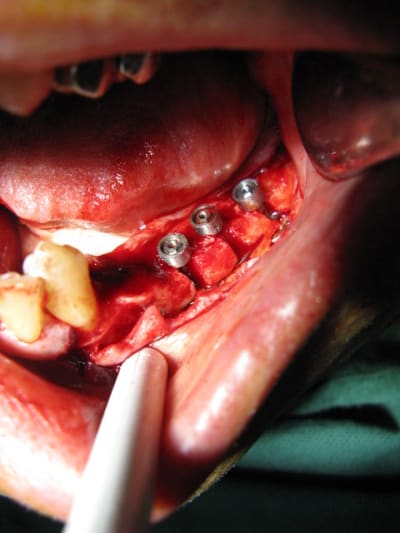

21 jours post-op

Oui patient très heureux même avec une petite "surcharge" implantaire selon certains ;-)